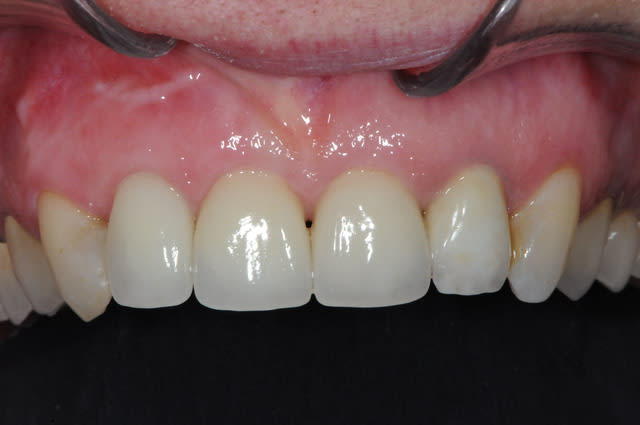

voici - voilà:

photo

1: j+ 2 ou 3 jours

2: j+8 mois

3-4-5: j+ 2 ans

sur la photo 3 on voit à la gencive que l'aspect est moins granité au niveau du col.

c'était ça l'indice pour trouver Charlie.